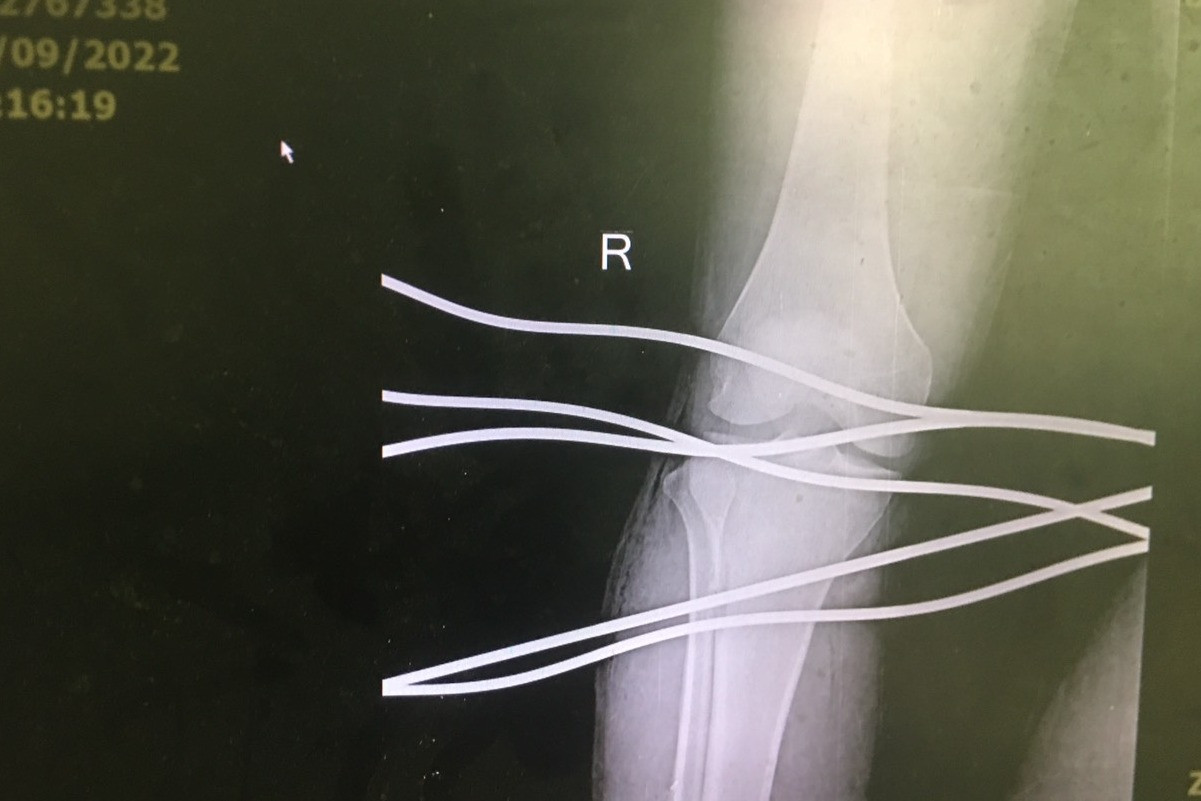

Phẫu thuật lấy 5 thanh sắt xuyên qua chân chàng trai 19 tuổi

Trong quá trình anh H. kéo cáp bằng máy tại công ty, 5 thanh sắt bắn ngược lại đâm vào chân bệnh nhân.